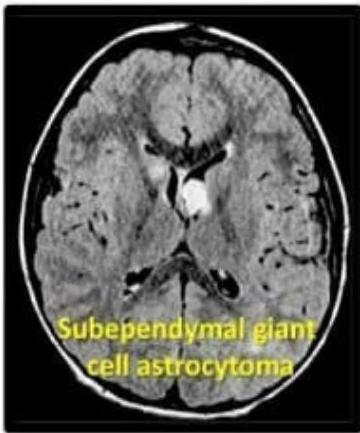

- Subependymal Giant Cell Astrocytoma (SEGA): Can cause obstruction of CSF outflow Hydrocephalus.

- Subependymal giant cell astrocytoma (SEGA)